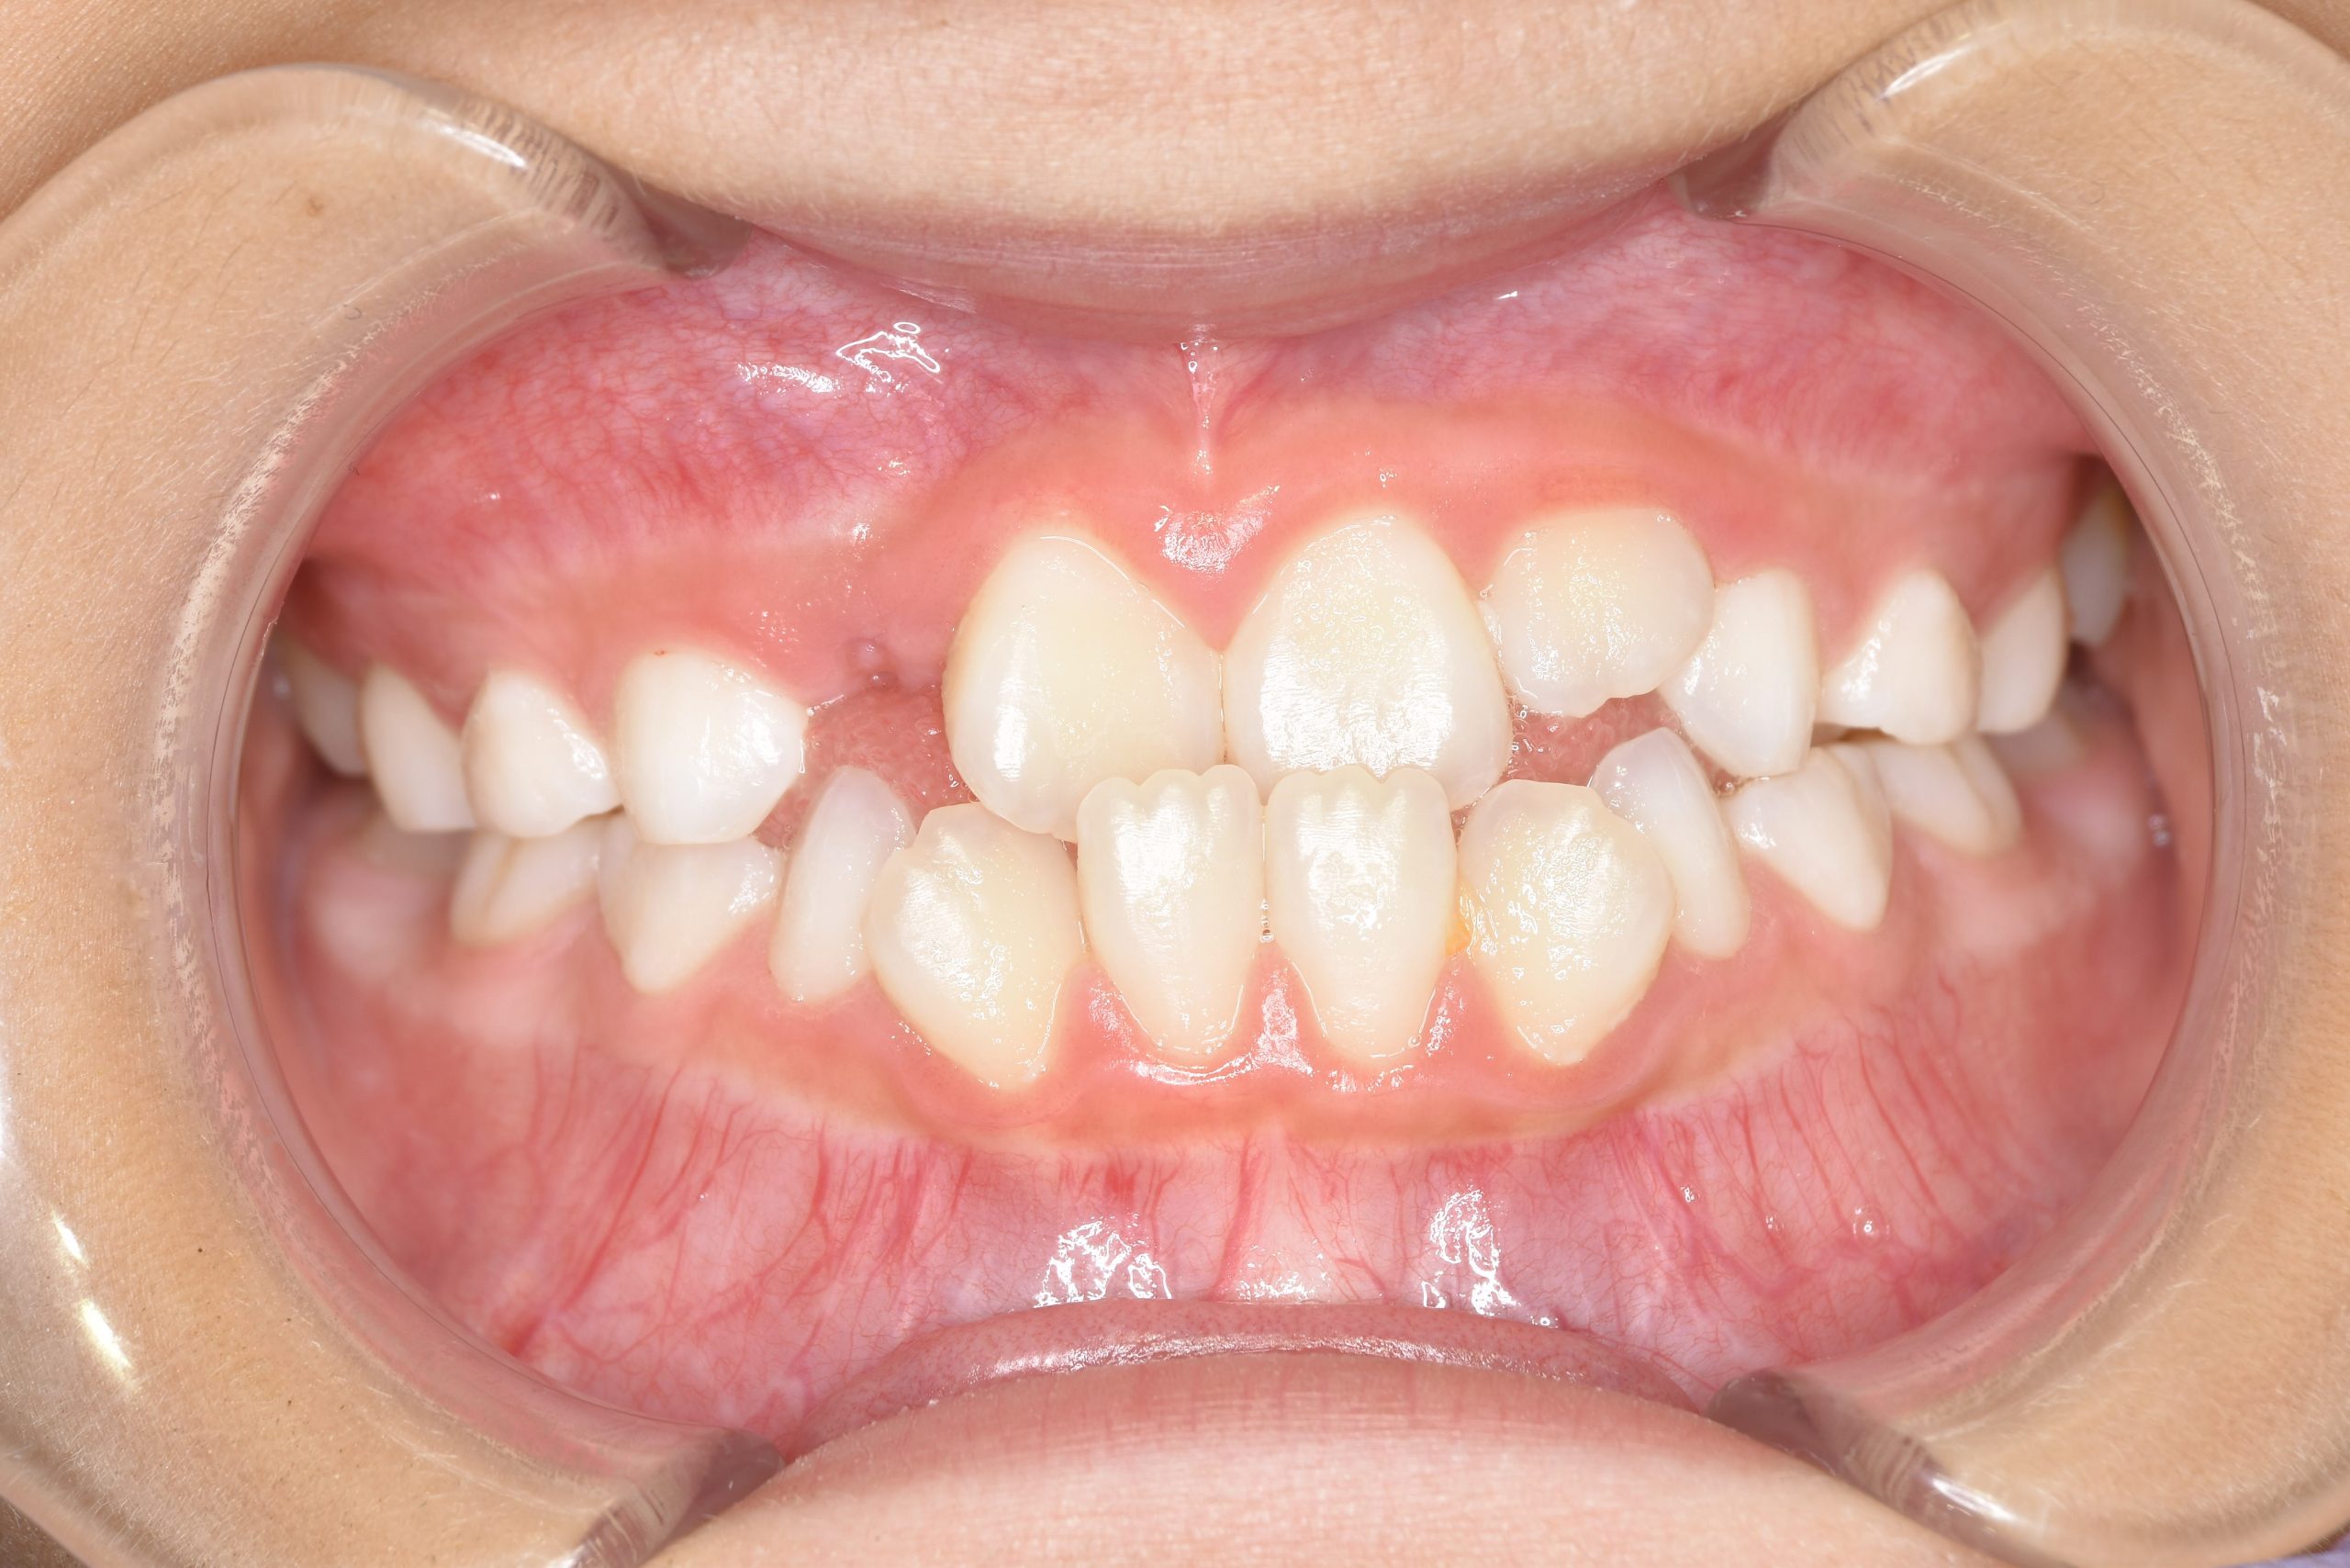

アフター

主訴 受け口

施術内容 上顎急速拡大装置と下顎リンガルアーチを用いて上下顎骨を拡大した。

上顎前方牽引装置を用いて上顎骨を前方に成長促進させた。

その後マウスピース型矯正装置で歯牙を配列し良好な咬合を獲得した。

治癒期間 2年9ヶ月間